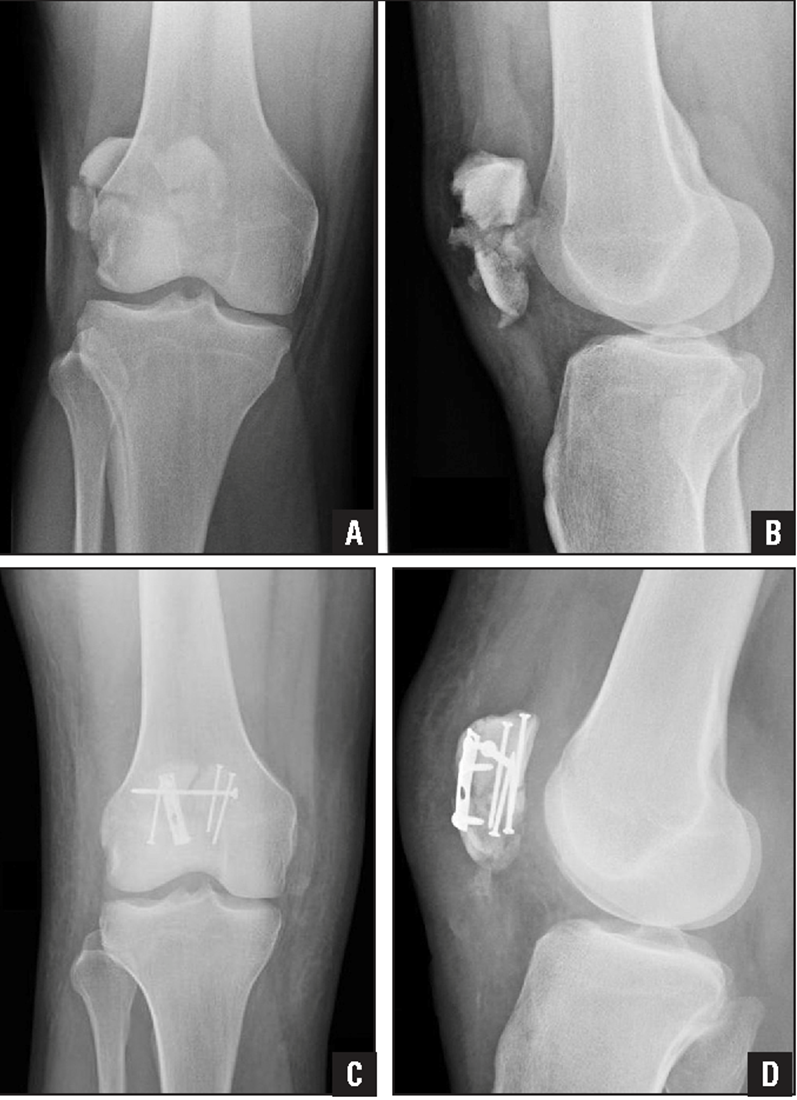

Osgood Schlatter

Incomplete separation or avulsion of the tibial tuberosity.

Cause: Repeated stress to tibial tuberosity growth plate

•stress will lead to the tendon pulling away

Complications: are uncommon, chronic pain or localized swelling,

bump in the area

Radiographic Appearance: prominent soft tissue swelling and an avulsed ossific fragment

Technical: No manual exposure factor change

Prognosis: good, resolves normally on its own once the bones

stop growing